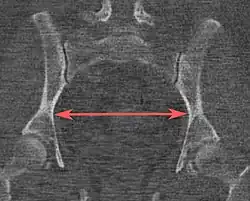

| Distância interespinhosa | ![]() |

![]() Plano axial |

A linha entre os pontos ósseos mais próximos das espinhas isquiáticas | 9,5 a 11,5 cm.[6] | |